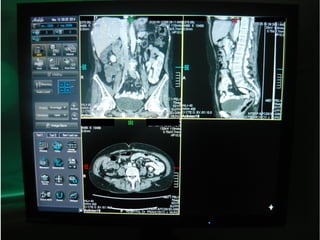

MPRMPR Reconstrucción Multiplanar

Es una deformación geométrica del volumen

de datos. No es 3D.

Suele ser la más utilizada. Permite visualizar el

volumen.

Las reconstrucciones multiplanares deben ser

calculadas a partir de voxels isotrópicos (voxels

con lados iguales en las tres dimensiones del

espacio)